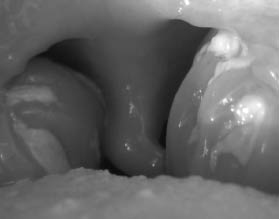

Αμυγδαλίτιδα και Στρεπτοκοκκική Αμυγδαλίτιδα

Οι αμυγδαλές είναι δύο λεμφαδένες που αποτελούν μέρος του ανοσοποιητικού συστήματος. Βρίσκονται στα πλάγια τμήματα του λαιμού και συμβάλλουν στην καταπολέμηση της μόλυνσης.